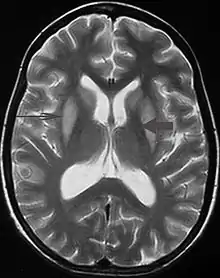

T2 weighted magnetic resonance scan image showing bilaterally symmetrical hyperintensities in caudate nucleus (small, thin arrow), putamen (long arrow), with sparing of globus pallidus (broad arrow), suggestive of extrapontine myelinolysis (osmotic demyelination syndrome)

It can be diagnosed clinically in the appropriate context, but may be difficult to confirm radiologically using conventional imaging techniques. Changes are more prominent on MRI than on CT, but often take days or weeks after acute symptom onset to develop. Imaging by MRI typically demonstrates areas of hyperintensity on T2-weighted images.